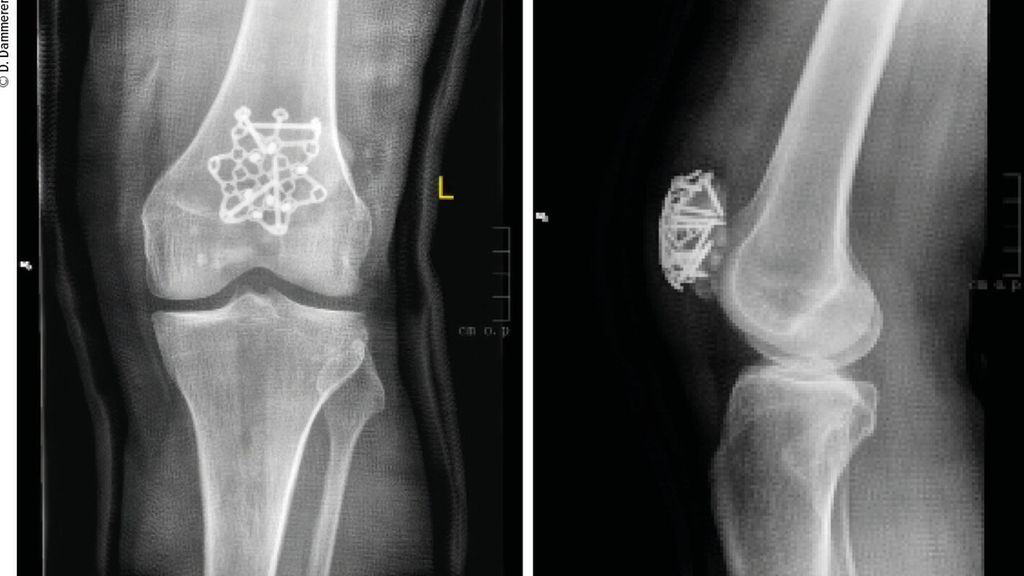

Die winkelstabile Sternplatte zur Behandlung von Patellafrakturen

Die Patellafraktur ist eine seltene (1%), aber komplikationsbehaftete Fraktur.1 Bei fast einem Drittel der Patienten kommt es postoperativ zu belastungsabhängigen Schmerzen, chronischen ...